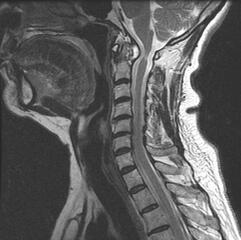

La columna vertebral padece de un desgaste a través del tiempo que la predispone a lesión. Nuestra misión es proveer respuestas en cuanto al origen y la historia natural de tu dolor. Nuestro equipo ayudará en la identificación de tu condición y te acompañara en el camino a recuperar tu calidad de vida.Condiciones médicas:Hernia discal cervical

Conducto cervical estrecho